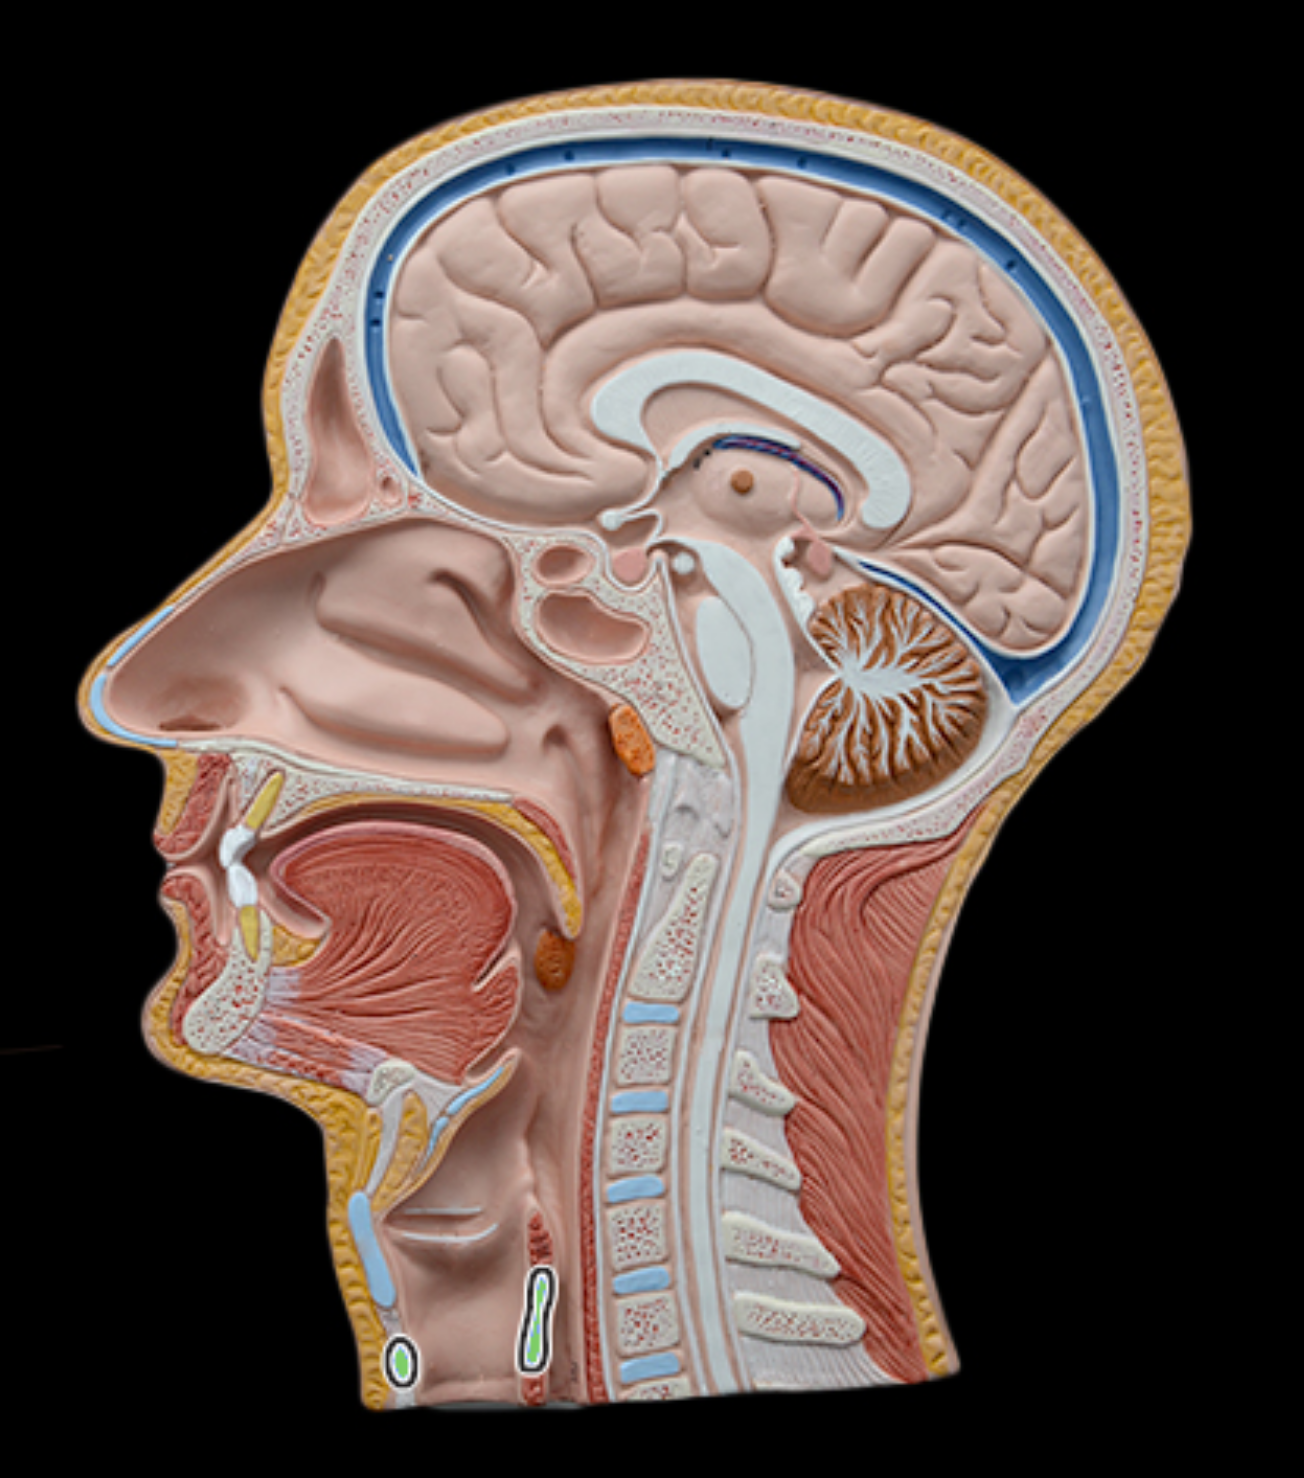

Pharyngeal tonsil

Lingual tonsil

Palatine tonsil